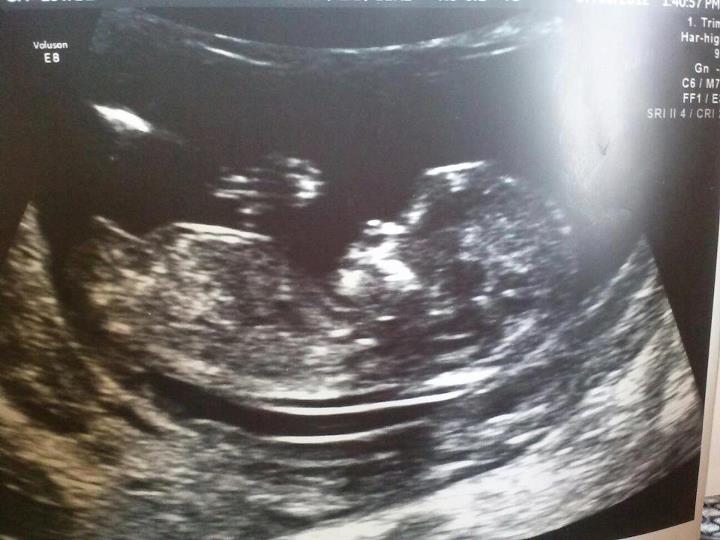

Attachment 4041 this was at my 12 week scan i was 12 weeks and 2-3days. what do you all think? Boy or girl? By the skull or nub theory. im starting to feel really stressed out about it. Plz someone who is good at this tell me what they think. thanks for looking.